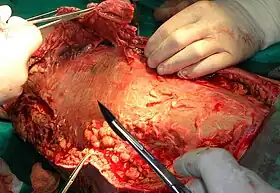

Surgery

Aggressive wound debridement should be performed early, usually as soon as the diagnosis of necrotizing soft tissue infection (NSTI) is made. Surgical incisions often extend beyond the areas of induration (the hardened tissue) to remove the damaged blood vessels that are responsible for the induration. However, cellulitic soft tissues are sometimes spared from debridement for later skin coverage of the wound. More than one operation may be used to remove additional necrotic tissue. In some cases when an extremity is affected by a NSTI, amputation may be the surgical treatment of choice. After the wound debridement, adequate dressings should be applied to prevent exposure of bones, tendons, and cartilage so that such structures do not dry out and to promote wound healing.[2]

Wound after aggressive acute debridement of NF

Wound after aggressive acute debridement of NF Necrotic tissue from the left leg surgically removed